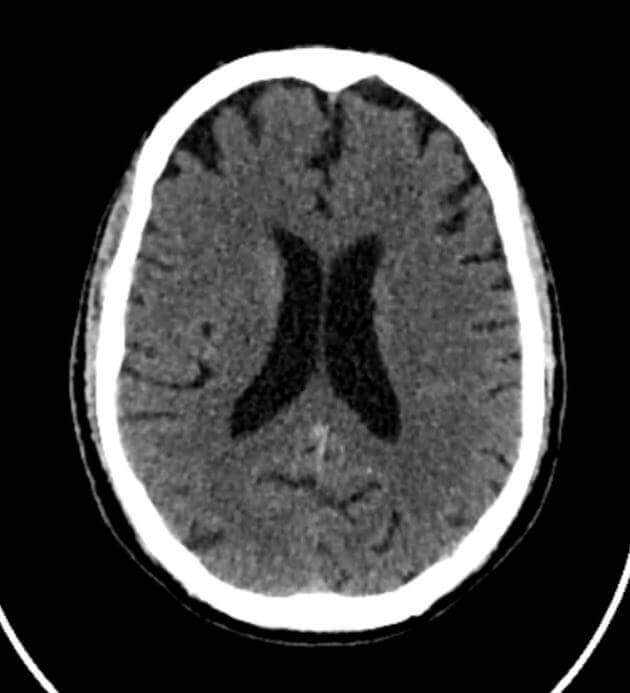

CT scans

A CT scan, or computed tomography scan, is a medical imaging test that uses X-rays and computer technology to create detailed images of the inside of the body.